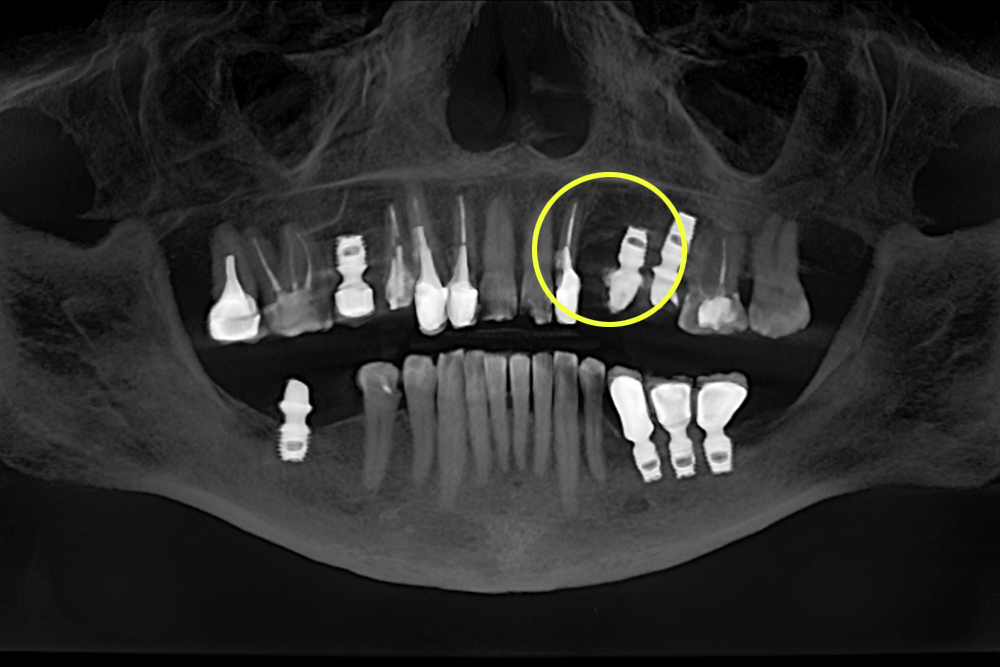

На КТ-снимке мы увидели, что один из имплантов слева на верхней челюсти не интегрировался в кость, был подвижным и спровоцировал воспалительный процесс в организме.